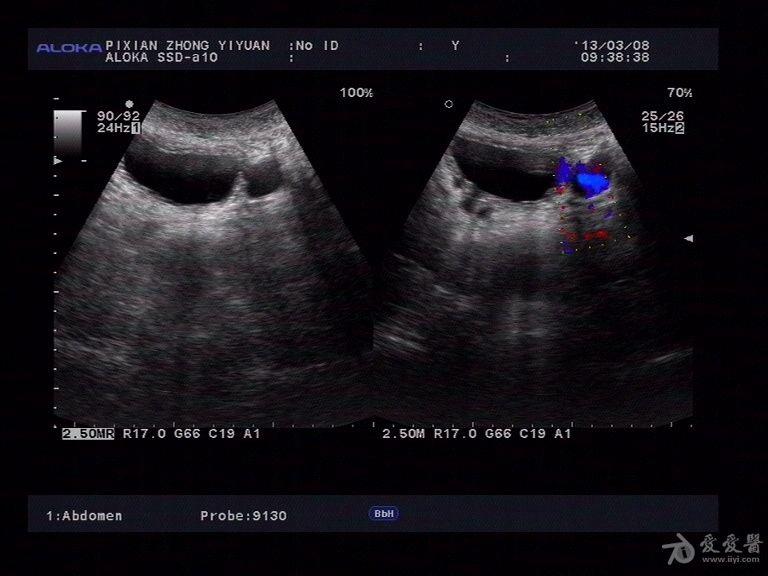

膀胱憩室并憩室内结石 - 超声医学讨论版 - 爱爱医医学论坛 - 爱爱医

图片尺寸768x576